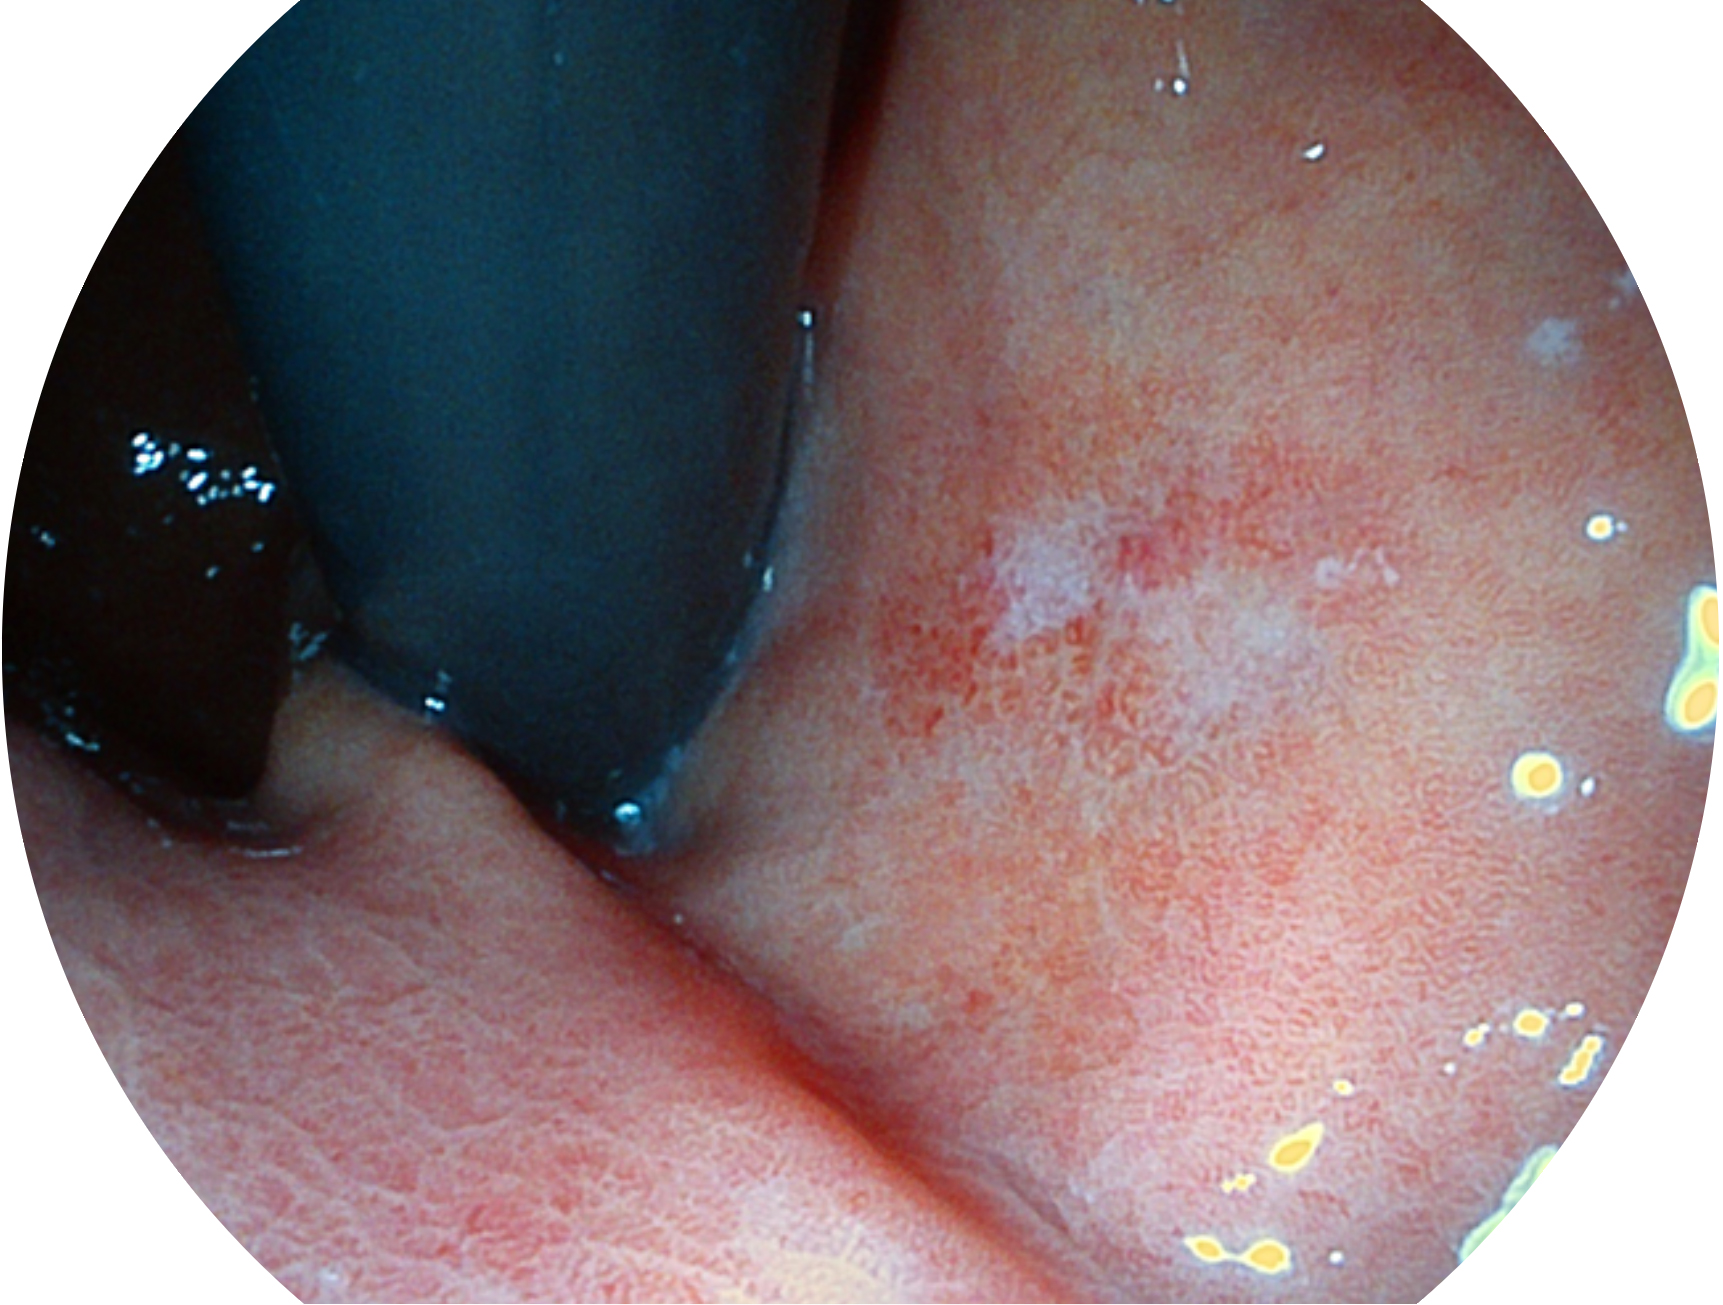

• 白光图像 VIST图像

与上一代VIST相比,摒弃了滤光转轮而直接采用光谱组合的方案,加入了血红蛋白吸收高峰与次高峰的蓝紫光和绿光光谱,更有利于黏膜血管吸收,突显浅表层血管和中层血管的对比度,因而具备更高的图像对比度,近景观察时,有助于微细结构变化及病灶边界的观察。